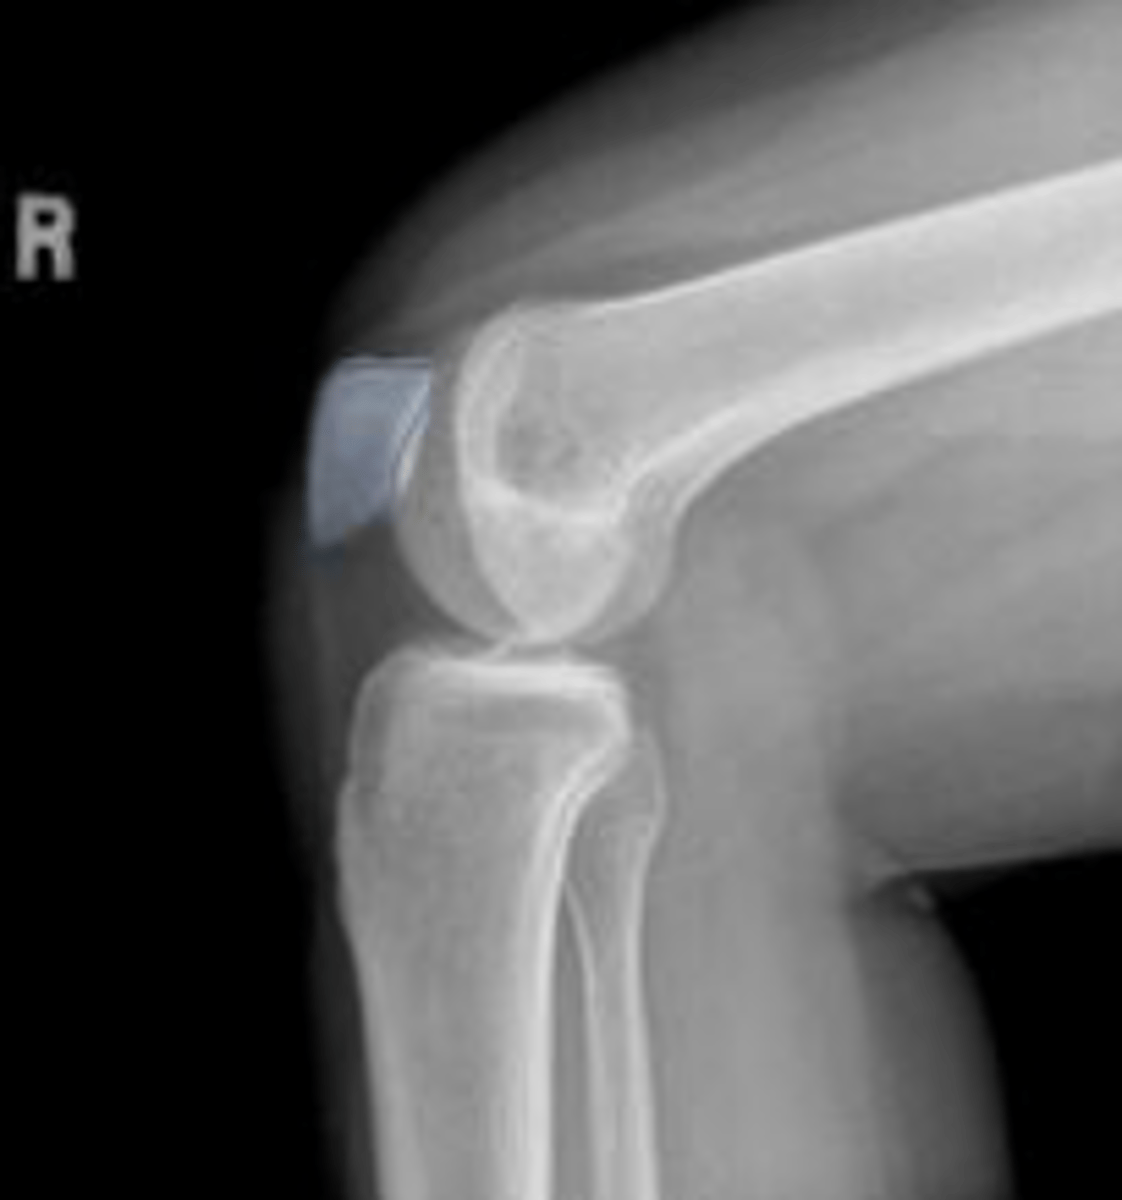

Lateral collateral ligament avulsion fracture of

the right knee

Lateral collateral ligament

What inserts at the location of the blue arrows?